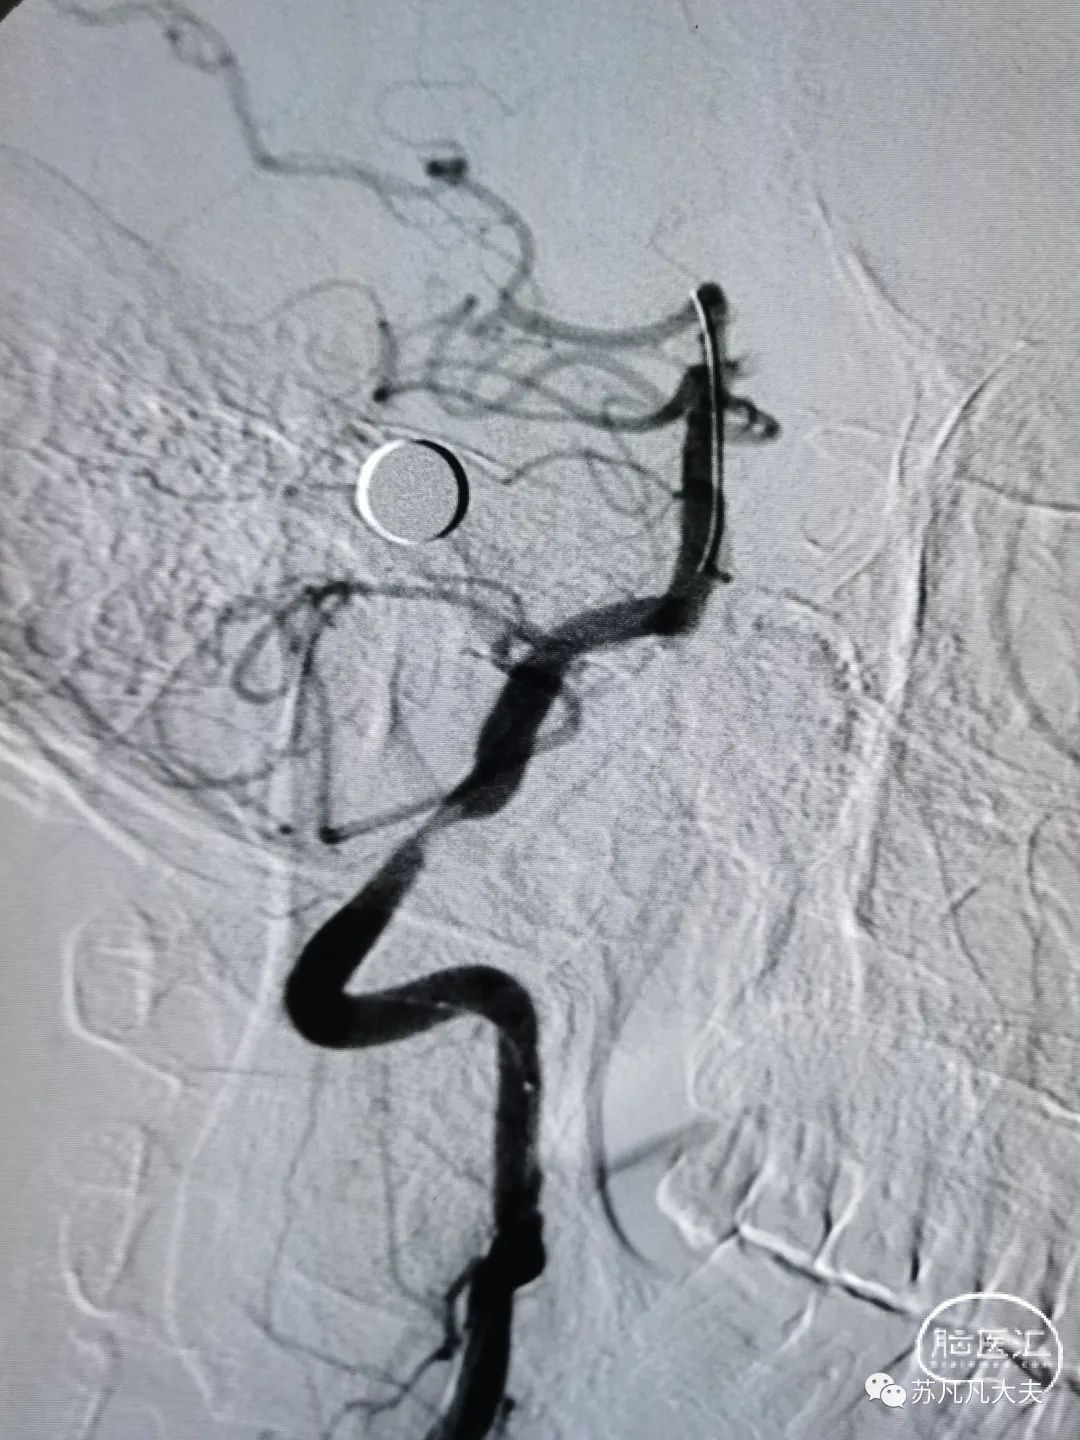

4/20取栓支架到位释放后造影

取栓后左侧大脑后动脉P1段再通

考虑患者大脑后动脉远端迂曲,继续取栓存在血管破裂出血风险,和家属交代后结束手术。

术后造影狭窄解除,颅内血供改善